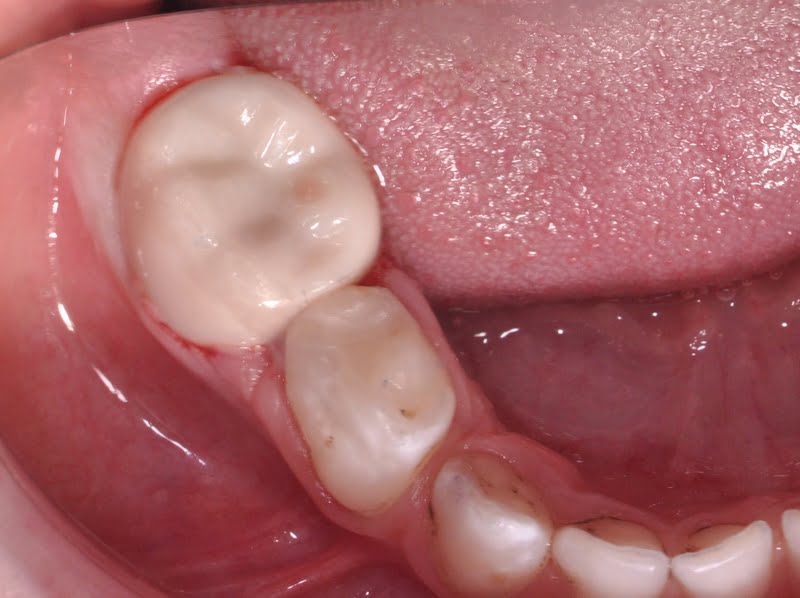

Foi realizado um exame clínico e radiológico inicial (fig. 1 a 3), tendo sido diagnosticada, entre outras lesões de cárie, uma lesão de cárie profunda com atingimento pulpar no segundo molar temporário inferior direito (fig. 3). Foi proposta a realização de uma pulpotomia com agregado trióxido mineral (MTA) e a colocação de uma coroa pré-formada. As várias possibilidades restauradoras foram apresentadas e discutidas com os pais, que decidiram optar pela colocação de uma coroa pré-formada de zircónia, por motivos estéticos.

Após a anestesia e a colocação do isolamento absoluto com dique de borracha (fig. 5) foi iniciado o preparo dentário para a colocação de uma coroa de zircónia pré-formada, seguindo as instruções do fabricante. Inicialmente, foi realizada uma redução da superfície oclusal de 1-2 mm, seguindo o contorno oclusal, com uma broca em chama de vela diamantada (fig. 6). De seguida, foi efetuada uma redução supragengival de todas as paredes dentárias com uma inclinação ligeiramente convergente para oclusal. Foram eliminados os contactos interproximais e toda a coroa clínica foi reduzida em cerca de 20-30%, seguido de um cuidadoso desgaste com uma broca em fio de faca diamantada da margem da preparação, cerca de 1-2 mm infragengival, para eliminar todas as margens ou degraus. Todas as linhas de ângulo foram ligeiramente arredondadas (fig. 7).